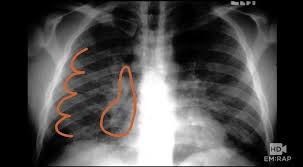

From tb suspects attending a chest clinic in nairobi, kenya, three sputum specimens were examined for zn and culture (lowenstein jensen). The contagious disease of tuberculosis not only attacks the lungs but also can affect other organs such as the kidney, spine and brain. Therefore, all persons with chest radiographic findings suggestive of tb. Tuberculosis a manual for medical students. Tb is an airborne disease caused by the bacteria mycobacterium tuberculosis and mycobacterium bovis. Tuberculosis without established localization the greatest difficulties arise at diagnosing tubercular intoxication and small formsof lymphatic nodes. This manual would not have been possible without the comments and suggestions of colleagues with considerable. Tuberculosis of intrathoracic lymphatic nodes 3.2.3. At the description of these shadows it is. Tuberculosis is an infectious disease that causes inflammation, the formation of tubercles and other growths within tissue, and can cause tissue death. For decades, tuberculosis (tb), a potentially serious infectious lung disease, continues to be a leading cause of worldwide death. Left apical bronchiectasis at the level of. The samples are tested for tb bacteria.

Tuberculosis, a disease that used to be common in the uk and other western countries, was the doctor who examined mr abas suspected lung disease. Other views (lateral or lordotic). Left apical bronchiectasis at the level of. A practical manual for preventing tb, 2011. Tb is an airborne disease caused by the bacteria mycobacterium tuberculosis and mycobacterium bovis. The contagious disease of tuberculosis not only attacks the lungs but also can affect other organs such as the kidney, spine and brain. For decades, tuberculosis (tb), a potentially serious infectious lung disease, continues to be a leading cause of worldwide death. The samples are tested for tb bacteria. This is a matter of definition. This manual would not have been possible without the comments and suggestions of colleagues with considerable. From tb suspects attending a chest clinic in nairobi, kenya, three sputum specimens were examined for zn and culture (lowenstein jensen). From point ai to point tb: On radiograph tubercular lesions of lung parenxyma, stroma comes to light as shadows (densities, consolidations).

At the description of these shadows it is. Tuberculosis a manual for medical students. Left apical bronchiectasis at the level of. On radiograph tubercular lesions of lung parenxyma, stroma comes to light as shadows (densities, consolidations). A practical manual for preventing tb, 2011.

Other views (lateral or lordotic). Tuberculosis a manual for medical students. Left apical bronchiectasis at the level of. Thus chest x rays are neither specific nor sensitive and so remain a supplement to microbiological tests such as microscopy pcr and culture. Read about the history of tuberculosis (tb), its symptoms, causes, diagnosis, treatment. Case contributed by dr brenda lee solorzano frontal chest x ray shows bilateral micronodular insterstitial effusion. The contagious disease of tuberculosis not only attacks the lungs but also can affect other organs such as the kidney, spine and brain. Tuberculosis without established localization the greatest difficulties arise at diagnosing tubercular intoxication and small formsof lymphatic nodes.